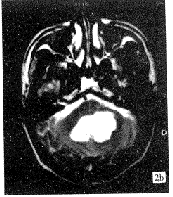

表现为长T1、T2者6例(图1),短T1,短、长T2信号2例。其中经压脂后信号由高变低者3例,而信号不均匀者多为不规则形(图2)。增强扫描采用SE-T1WI和3D SPGR两种方式,完全不强化6例,少许强化1例,环形强化1例。病灶位于CPA者听神经均显示正常,2例可见听神经受压,与临床听力下降相符。类圆形病灶有明显占位效应,邻近结构可见受压改变。不规则形病灶占位征象不明显,可见沿蛛网膜下腔生长。颅底骨质未见明显受侵。

图2 (a)横断面T1WI,(b)横断面T2WI;后颅窝可见形态不规则之肿瘤,呈长T1、长T2信号,其内信号不均匀,边缘亦欠光整。